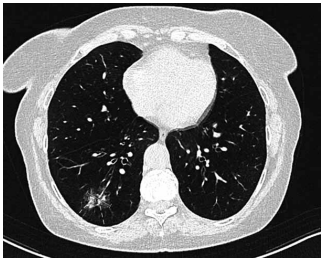

Mulher de 72 anos é atendida em consulta de retorno. O

histórico é positivo para tabagismo de 25 anos-maço e

DPOC (grau 3; grupo B). Recentemente, ela teve pneumonia com infiltrado persistente no lobo inferior direito

observado na radiografia de tórax. A paciente foi tratada

com antibiótico. Seu peso permaneceu estável, e ela não

apresentou febre ou sudorese noturna. Após seis semanas, uma radiografia de tórax de acompanhamento não

apresentou alterações. Uma tomografia é então realizada

e mostrada a seguir (a parte sólida do nódulo é de 7 mm):

(Arquivo pessoal; imagem usada com autorização)

Quanto a essa paciente, o próximo passo mais apropriado é